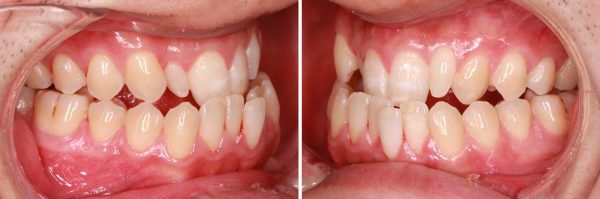

ワイヤーとゴムを使用した治療により反対咬合を修正しました。

2017年の6月27日にスタートして 2018年の10月2日に 終了 しました。

治療期間 16か月

受け口は すっかりと治り 口もとも大きく変わりました

「自信がなさそうな 表情だった息子が自信をつけて すっかりと 男前になった」と

お母さまは とても喜んで頂けました。

素敵な笑顔になりました!(#^.^#)

これから大学に進学されるそうです。

自信あふれる 笑顔で 明るい青春をお過ごしください (*´▽`*)

16歳 男性 叢生を伴う反対咬合 治療期間16か月 唇側矯正装置(ホワイトワイヤー)拡大装置(ワイヤー型)非抜歯治療 参考治療費 約65万円 (精密検査から終了まで) 矯正治療に伴う副作用の歯肉退縮、知覚過敏、歯根吸収などは認められませんでした。